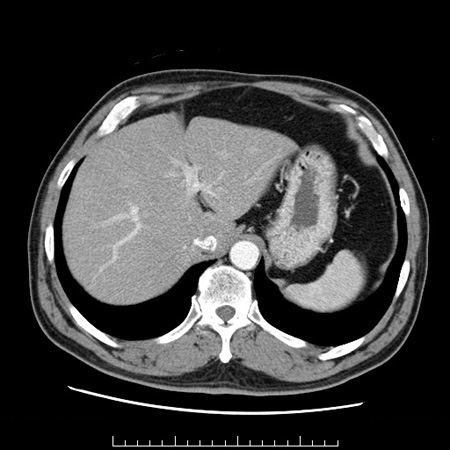

肝膿瘍